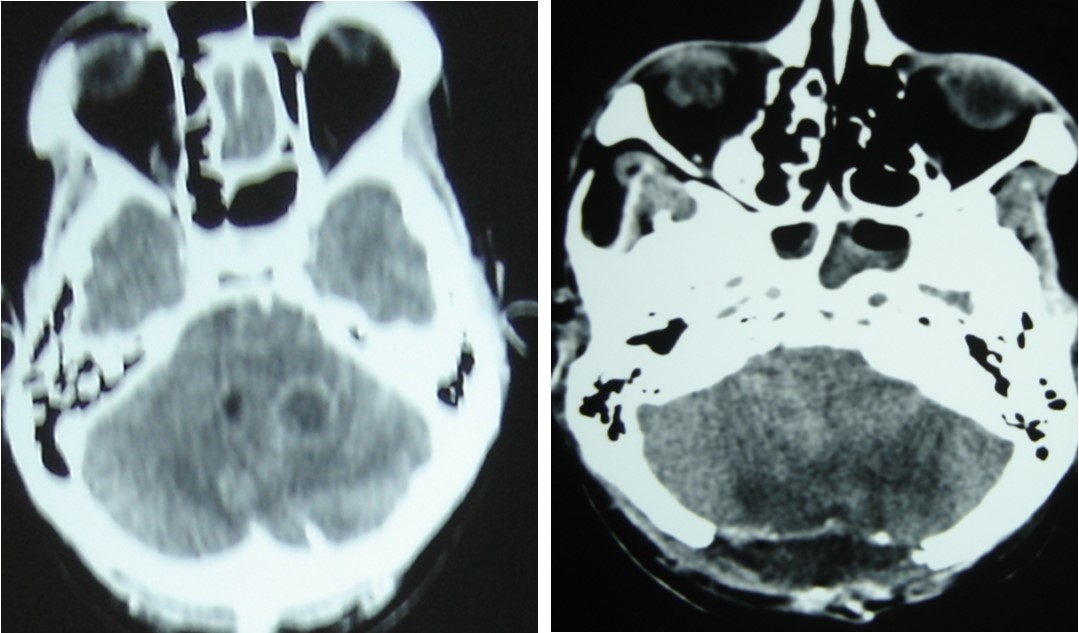

Patient was placed on intra veinous amphotéricin B but this was complicated with acute active hydrocephalus warranting external ventricular drainage (Figure 3). Subsequently, he developped staphylococcal meningitis as day 8 post op, treated with intra veinous vancomycin. Patient developed renal insufficiency and hyperosmolar non ketotic coma for an unknown diabetis for which amphotéricine B therapy was stopped. His neurological status deteriorated with a Glasgow coma scale (GCS)7/15. Posterior fossa surgery was performed with excision of the fungal abscess (Figure 4) and Voriconazol was instituded post operatively for fungal therapy with improvement of the neurological status to GCS 13/15. But the patient succumbed to acute cardiac failure.

Figure 4.cerebral CT scan pre operative (A) and post operative (B) after posterior fossa surgery with total removal or abscesses